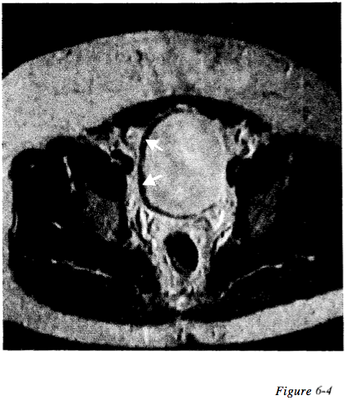

Question 59

Question

Figure 6-4 displays an example of what type of artifact

Answer

• Phase mismapping

• Aliasing

• Chemical shift

• Cross excitation